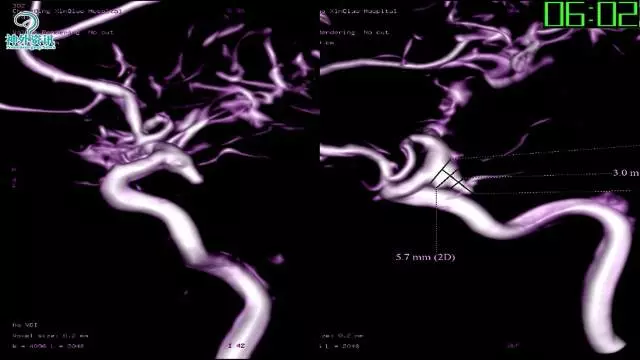

今天为大家分享的是“强生医疗CNV-神经介入专栏”第三十六期,由重庆第三军医大学附属新桥医院神经外科刘俊带来的“Galaxy弹簧圈在不规则动脉瘤中的临床应用”精彩讲课视频及PPT,欢迎观看。文章仅代表作者个人观点,如有不同见解,欢迎同道斧正!